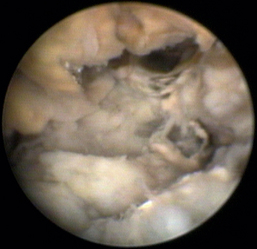

Rhinoscopic sequence imaging of TNC debridement of a feline caudal nasal and nasopharyngeal adenocarcinoma is depicted in Figures 19-63 through 19-69.

image

Figure 19-63 Transnares curettage sequence: feline nasal adenocarcinoma of the right caudal nasal cavity and nasopharynx, evaluation of the tumor extent, tumor debridement, and reevaluation of lumen patency after the procedure.

Figure 19-64 Right caudal nasal cavity adenocarcinoma at the level of the choana.